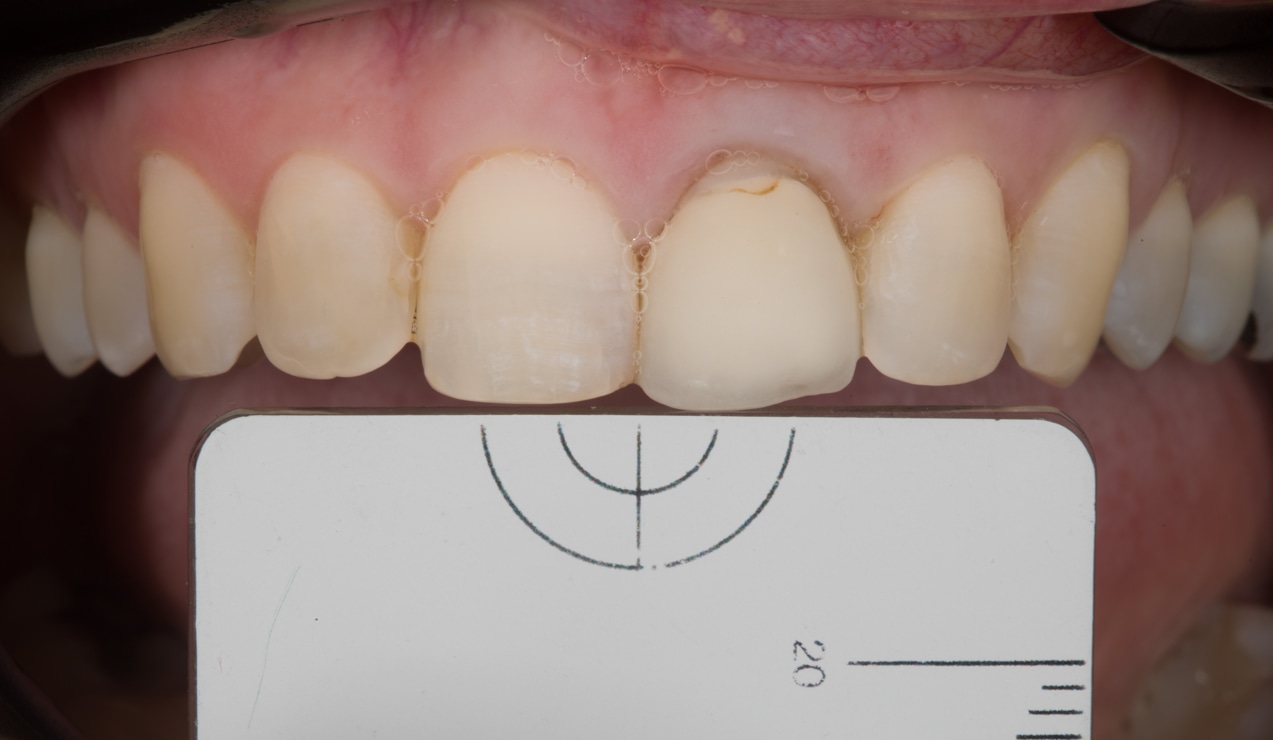

Minimal Prep Veneers to correct a discoloured tooth and improve form